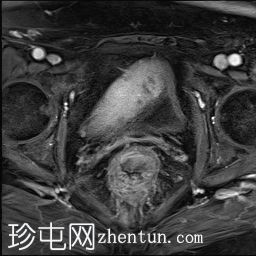

轴位T2加权像

该T2脂肪抑制磁共振成像显示右髂血管旁有一管状结构,终止于回盲部。